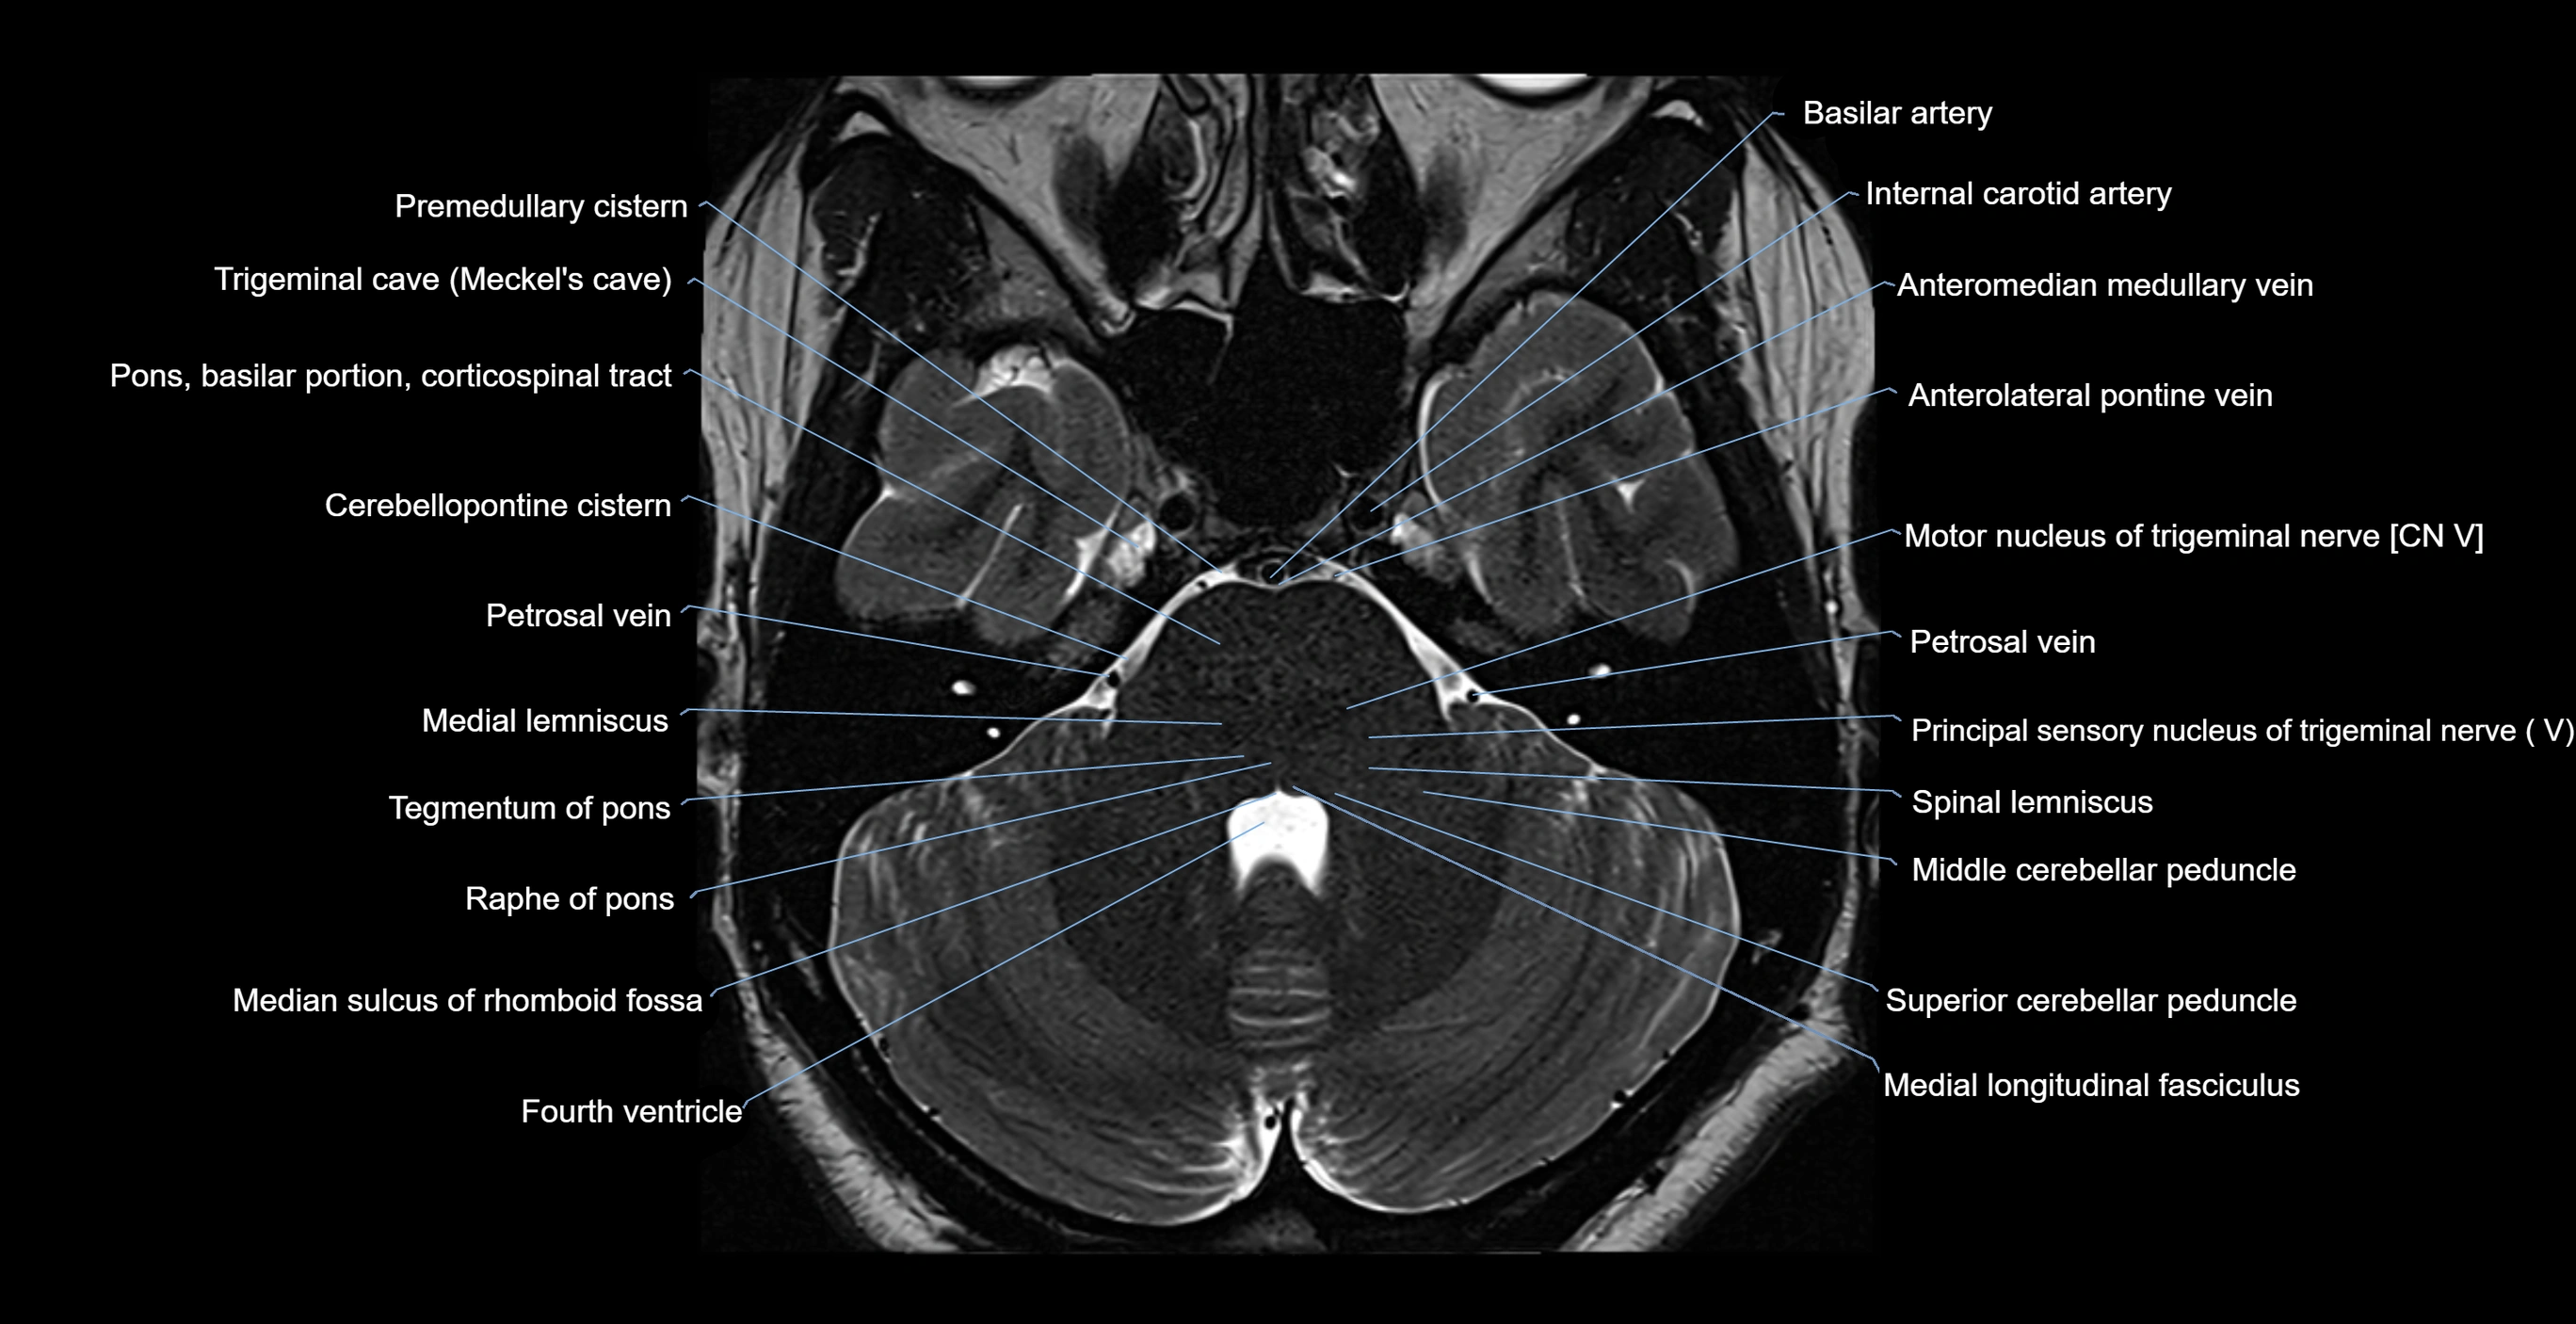

- Anterolateral pontine vein

- Anteromedian medullary vein

- Cerebellopontine cistern

- Medial lemniscus

- Medial longitudinal fasciculus

- Median sulcus of rhomboid fossa

- Median sulcus of the 4th ventricle

- Middle cerebellar peduncle

- Motor nucleus of trigeminal nerve

- Nucleus reticularis tegmenti pontis

- Petrosal vein

- Pons (basilar portion)

- Pontocerebellar cistern

- Premedullary cistern

- Principal sensory nucleus of the trigeminal nerve

- Principal sensory nucleus of trigeminal nerve

- Raphe of pons

- Spinal lemniscus

- Superior cerebellar peduncle

- Tegmentum of pons

- Trigeminal cave

- Trigeminal ganglion

- Trigeminal nerve (Cranial nerve V)